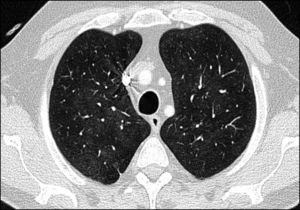

Case ReportThe patient was a 61-year-old man with a personal history of asthma who was diagnosed with AOSD in October 2011. He was initially treated with nonsteroidal anti-inflammatory drugs (NSAID). After 1 month, glucocorticoid (GC) therapy was started because of the development of skin involvement. In March 2012, subcutaneous methotrexate (MTX) was added as a steroid-sparing agent, and was escalated up to 25mg a week. For 2 years, a good control of the disease was achieved and maintained, making it possible to reduce the prednisone dose to 2.5mg/day. However, in November 2014, the patient experienced a severe joint and cutaneous flare that required hospital admission and an increase in corticosteroid therapy. After 1 month, the decision was made to initiate treatment with tocilizumab (TCZ) because of persistent arthralgia, fever and neutrophilic leukocytosis with hyperferritinemia, despite the treatment with MTX and high-dose oral GC. Three weeks after receiving the first and only dose of TCZ at 8mg/kg body weight, he presented to the outpatient clinic with dyspnea on moderate exertion. There was no evidence of infection or cardiac decompensation. The only noteworthy finding on physical examination was a baseline oxygen saturation (SO2) of 93%. An emergency chest radiograph (Fig. 1A) showed a faint image of bilateral interstitial involvement and the patient was referred to the emergency department. The results of the laboratory analyses performed there included a slightly decreased partial pressure of oxygen (PO2) (70.900mmHg), leukocytosis (13.54×103/μL), neutrophilia (11.93×103/μL), lymphopenia (0.59×103/μL), C-reactive protein < 0.5mg/L and elevated D-dimer (1.77μg/mL). The electrocardiogram was normal. Computed tomography (CT) angiography served to rule out pulmonary thromboembolism. However, the lung window (Fig. 2) revealed an increased ground glass density, predominantly in middle and upper lobes, suggestive of alveolar inflammation. In agreement with the pulmonology department, and given that the clinical signs were mild at that time, the decision was made to carry out pulmonary function tests (PFT), to perform a clinical reevaluation over the following days and to discontinue treatment with MTX and TCZ, as we suspected their possible implication in this condition. He returned 2 days later, complaining of a significant deterioration in his clinical status, with the development of fever and a dry cough, and was unable to complete the scheduled PFT. On the other hand, he had been taking amoxicillin/clavulanic acid for the preceding 2 days because of a dental abscess. A chest radiograph performed at that time (Fig. 1B) showed an increase in diffuse density in the region of the hilum and base of the lung. He was admitted to the hospital to complete the study and begin treatment with prednisone at 30mg/day. The laboratory tests revealed a ferritin level of 4023ng/mL (previously 1997ng/mL), C-reactive protein at 17.7mg/L, leukocytosis at 15,280×103/μL, neutrophils at 12,360×103/μL and lymphocytes at 1870×103/μL, there being no other noteworthy findings. Bronchoalveolar lavage revealed an increase in the percentage of lymphocytes, with normal lymphocyte subsets and negative results for cytology and cultures for fungi, cytomegalovirus, herpes, influenza/parainfluenza and adenovirus, and negative staining of acid-alcohol fast bacilli. The PFT disclosed a restrictive change with a reduced diffusing capacity (48%), which was not corrected for at alveolar volume. During his hospital stay, the patient initially required oxygen therapy at 1.5bpm and, subsequently, treatment with subcutaneous anakinra was introduced at 100mg/day. Within a few days, he began to show progressive improvement in both clinical signs and laboratory results, as well as normalization of the radiographic pattern after 10 days and, after 1 month, control of ferritin and CT images.